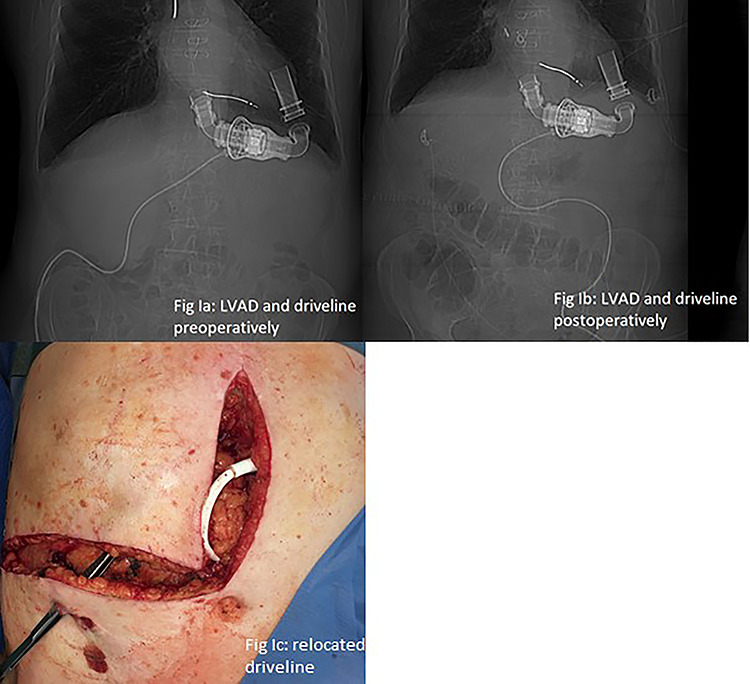

Because driveline was located in the way of planned laparotomy, surgery was scheduled as an interdisciplinary approach.

LVAD-driveline was then dissected from scarring tissue, disconnected from its controller for 30 s and repositioned in the left upper quadrant. Circulation was maintained with the use of epinephrine and norepinephrine. Figure 2a and b show preoperative and postoperative driveline positions. Figure 2c shows relocated driveline position and former driveline exit.

Figure 2.

(a and b) LVAD and driveline in preoperative and postoperative CT scan scout. (c) Relocated driveline during laparotomy, forceps in former driveline exit.